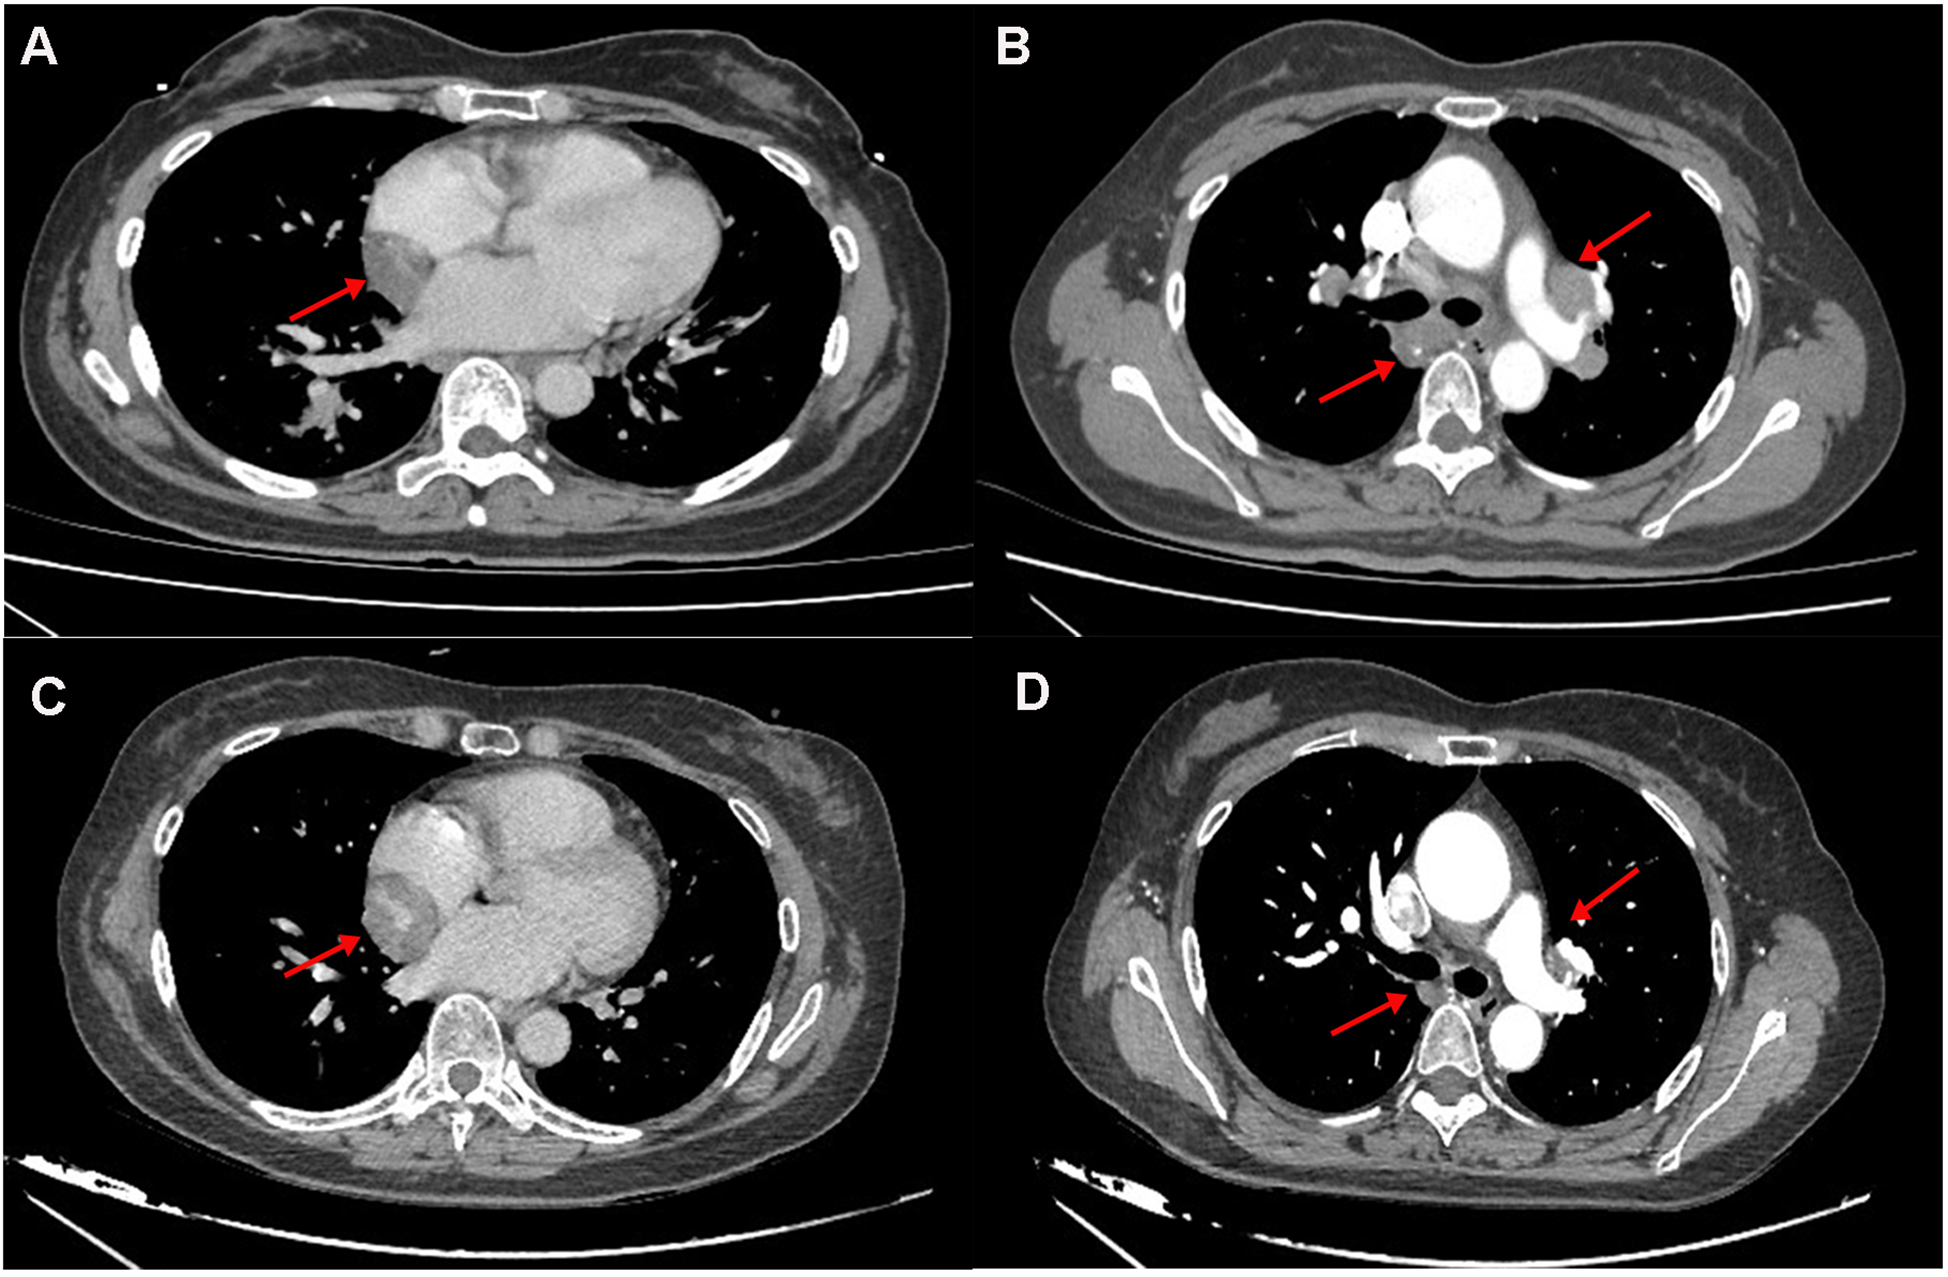

A 54-year-old woman presented with incidental findings on a 2022 surveillance chest computed tomography (CT), revealing pulmonary nodules and mediastinal lymphadenopathy alongside a 3.3 × 2.4 cm lesion at the atrioventricular groove (Figures 1A,B). Subsequent integrated positron emission tomography-computed tomography (PET-CT) suggested potential neoplastic pathology. Diagnostic confirmation of pulmonary sarcoidosis was established via endobronchial ultrasound-guided transbronchial needle aspiration (EBUS-TBNA) of mediastinal lymph nodes and percutaneous lung biopsy in 2022. The patient initiated protocol-based oral methylprednisolone therapy with gradual tapering, achieving discontinuation after 18 months. Six months post-discontinuation, surveillance imaging demonstrated recurrent mediastinal lymphadenopathy, prompting reinitiation of methylprednisolone, which induced lymph node regression. Long-term oral methylprednisolone (2 mg daily) was initiated as maintenance therapy. Throughout this period, the atrioventricular groove lesion exhibited no significant interval changes.During an April 2025 follow-up, transthoracic echocardiography detected a solid mass at the right atrial roof demonstrating interval progression compared to prior studies. The patient remained asymptomatic without palpitations, chest tightness, or dyspnea. Medical history was negative for hypertension, coronary artery disease, or tobacco use. At the time of physical examination, the patient was afebrile. His heart rate was 82 beats/min, respiratory rate was 18 breath/min, and blood pressure 108/78 mmHg, SpO2 was 98% (room air). Cardiopulmonary examination was unremarkable, with no evidence of jaundice, petechiae, or scleral icterus on integumentary and ocular inspection; no palpable lymphadenopathy was detected in superficial nodal basins, and bilateral eyelids were symmetric without visual disturbances.

Figure 1

(A,B) the 2022 chest CT revealed a hypodense lesion in the interventricular groove and hilar lymphadenopathy. (C,D) The 2025 CT revealed progressive enlargement of a mass within the atrioventricular groove (measuring 3.3 cm vs. 4.1 cm in 2022), with concurrent regression of bilateral hilar lymphadenopathy.

Laboratory studies revealed mild elevation of gamma-glutamyl transferase with otherwise unremarkable findings as detailed in Table 1. Contrast-enhanced chest computed tomography (CT) demonstrated a well-demarcated 4.1 × 2.7 cm mass adjacent to the right atrial roof, exhibiting a mean attenuation of 38 Hounsfield units (Figures 1C,D). 24 h ambulatory electrocardiography documented occasional atrial and ventricular premature complexes accompanied by transient horizontal ST-segment depression (0.05 mV in leads II, III, aVF, V5, V6). The right atrial mass revealed refractoriness to glucocorticoid therapy on retrospective chest CT review and exhibited interval progression on recent surveillance imaging, its clinical behavior was incompatible with a singular CS pathology. To achieve definitive histopathological diagnosis and guide subsequent therapeutic intervention, multidisciplinary shared decision-making with the patient and family culminated in proceeding with surgical resection. Preoperative coronary angiography showed no significant stenosis, while transesophageal echocardiography (TEE) revealed a 38 × 29 × 27 mm hypoechoic mass at the right atrial roof with distinct borders, broad-based attachment, regular contours, and absence of internal vascular flow. On May 28, 2025, cardiac tumor resection under general anesthesia was performed. Intraoperative exploration identified an intrapericardial mass (30 × 25 mm) with firm consistency, transversing the interatrial groove and exhibiting firm adhesions to bilateral atrial walls (Figure 2). Postoperative TEE confirmed complete resection without evidence of residual mass. Histopathological analysis of the excised atrial mass identified a cavernous hemangioma with granulomatous inflammation (Figure 3). Special staining analyses demonstrated comprehensively negative results across all performed assays: Periodic acid-Schiff (PAS), acid-fast bacilli (AFB) stain, silver stain, and Gram stain showed no pathological reactivity. Additionally, polymerase chain reaction (PCR) testing for Mycobacterium tuberculosis complex yielded negative results, further excluding mycobacterial involvement.